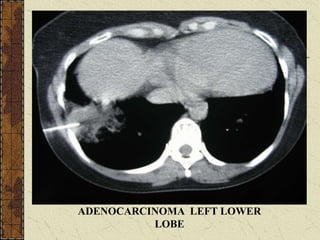

ADENOCARCINOMA LEFT LOWER

LOBE